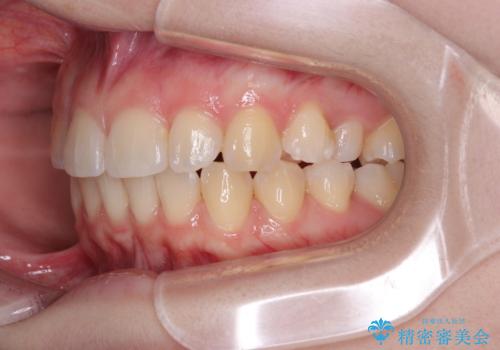

左上の前歯が出ているのが気になる 審美装置による非抜歯ワイヤー矯正

1年と少しで矯正治療を終えることができ患者様は大変満足されました。